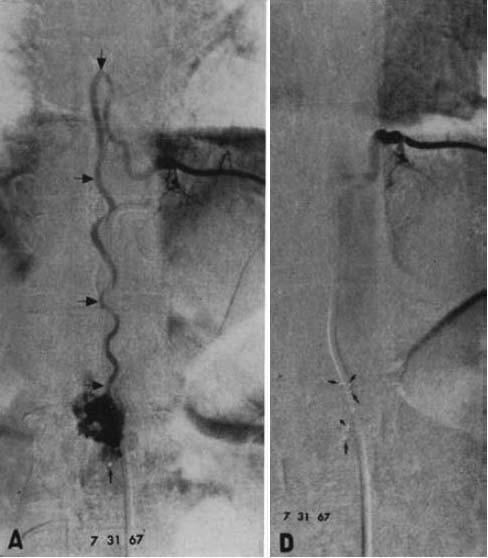

図5.(左)冠動脈造影後,穿刺部の血栓症.大腿動脈の起始部閉塞.(右)ストレプトキナーゼ投与24時間後.微小血栓を残して大腿動脈が大腿動脈の血流が回復している.さらに動注を継続し,45時間,30万単位の投与で血栓は完全に溶解した.

【要旨・解説】IVRによる血栓溶解療法の初報である.この時点でストレプトキナーゼ,ウロキナーゼの経静脈性全身投与の有効性は証明されていたが,これには10万単位/時を必要とし,全身性副作用ヘの懸念から普及していなかった.初めて,ストレプトキナーゼを経カテーテル的に,動脈内に直接投与してその有用性を示したのがこの論文である.

対象はカテーテルによる血管拡張術後7例,動脈硬化性閉塞7例,その他3例の計17例で,下肢15例,上肢2例である.カテーテルを血栓の直上に置くか,あるいは血栓内に刺入して,自動注入器でストレプトキナーゼを注入する.投与速度は5,000単位/時を標準とし,症例に応じて1~数日,最長2週間持続投与している(図5).結果は,術後の急性期血栓の成績は良好であるが,ある程度時間を経た血栓は不成功であった.

図6.急性心筋梗塞.(上)左冠動脈回旋枝の閉塞.(下)ストレプトキナーゼ冠動脈内投与後.回旋枝が良好に造影されている.

【要旨・解説】急性心筋梗塞で,冠動脈内に直接ストレプトキナーゼを動注し,治療に成功した初の報告である.それまでも,経静脈性の全身投与による治療の試みはあったが,その有効性が確認されていなかった.

対象は5例の急性心筋梗塞例で, いずれも緊急入院後,まずニトログリセリンを冠動脈に投与し,直後よりストレプトキナーゼをまずボーラスで1~2万単位,その後15~60分かけて1,000~2,000単位/時で持続動注し,全例で開存,臨床症状の軽快ないし消失が得られた(図6).治療経過中に冠動脈造影を頻繁に繰り返して,再疎通の状態を確認している.